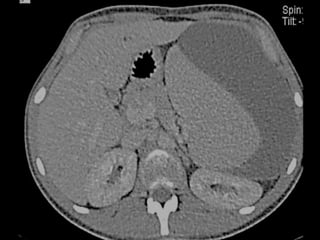

La rotura espontánea del bazo es una causa rara pero potencialmente letal de dolor abdominal que puede deberse a alteraciones congénitas, infecciones, enfermedades metabólicas, neoplasias, inflamación o alteraciones vasculares. Los síntomas incluyen dolor abdominal que se generaliza, distensión abdominal y signos de irritación peritoneal. El diagnóstico se realiza mediante cuadro clínico, exámenes de laboratorio, placa de abdomen, ecografía, lavado peritoneal o TC, y el tratamiento implica líquidos intra